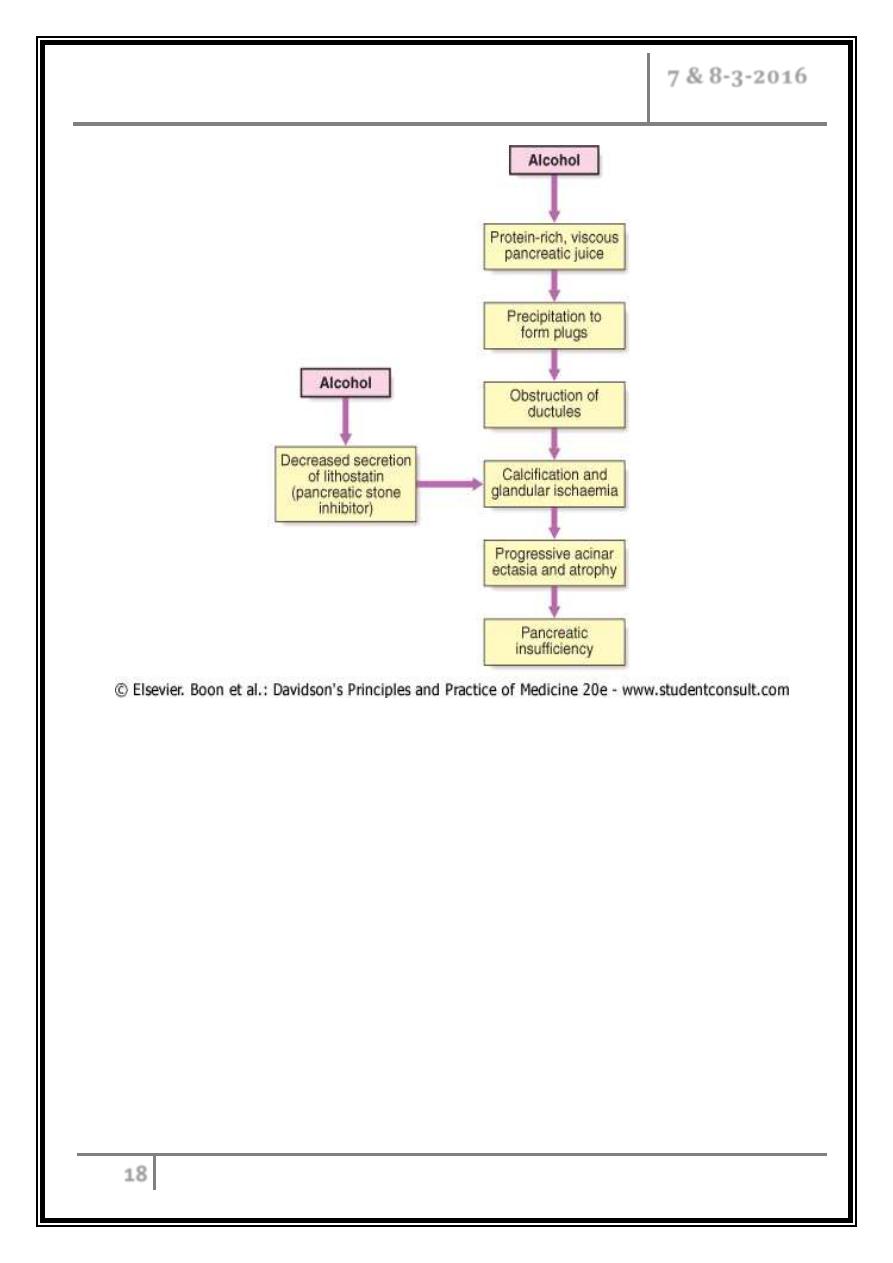

Pathophysiology of chronic pancreatitis